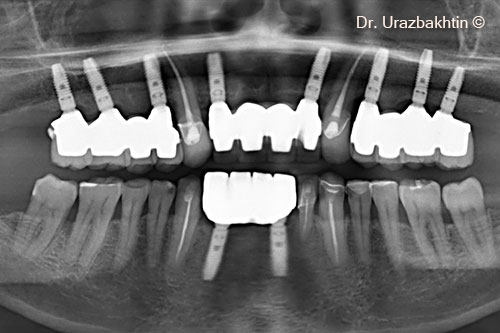

Tăng chiều cao xương hàm bằng kỹ thuật cắt xương ngang vùng hàm

Một bệnh nhân nam (77 tuổi) cần phẫu thuật nâng cao chiều dọc xương hàm.